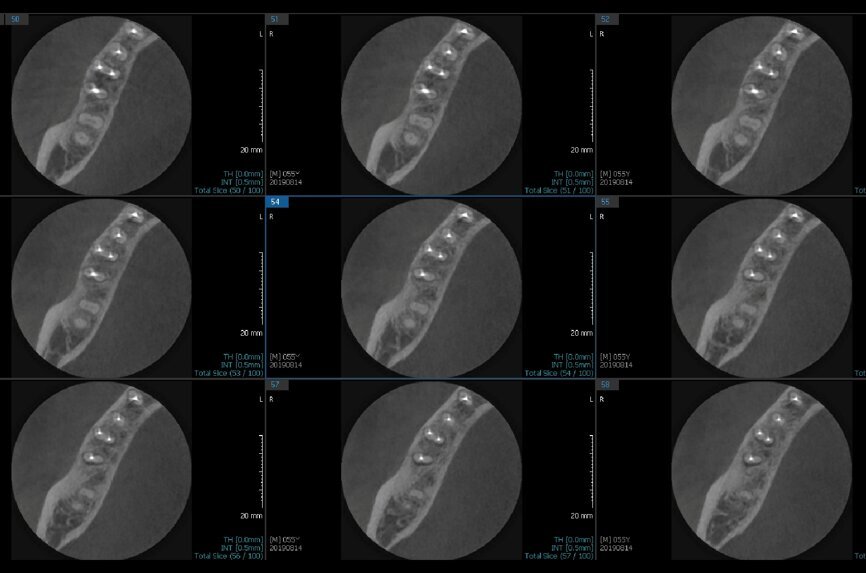

Fig. 6a: Post-op CBCT images of tooth #46 showing adequately obturated canals at all levels to the working length and sealing of the furcation defect.

Fig. 6b: Post-op CBCT images of tooth #46 showing adequately obturated canals at all levels to the working length and sealing of the furcation defect.

Fig. 6c: Post-op CBCT images of tooth #46 showing adequately obturated canals at all levels to the working length and sealing of the furcation defect.

Fig. 6d: Post-op CBCT images of tooth #46 showing adequately obturated canals at all levels to the working length and sealing of the furcation defect.

Fig. 6e: Post-op CBCT images of tooth #46 showing adequately obturated canals at all levels to the working length and sealing of the furcation defect.

Fig. 6f: Post-op CBCT images of tooth #46 showing adequately obturated canals at all levels to the working length and sealing of the furcation defect.

Fig. 6g: Post-op CBCT images of tooth #46 showing adequately obturated canals at all levels to the working length and sealing of the furcation defect.

At the next appointment, the temporary restoration was removed, and the hardness of the MTA was checked. The margins of the defect were also closely checked under the dental operating microscope to rule out any leakage. Finally, a thin layer of light-polymerising glass ionomer cement liner was placed over the MTA. Etching and bonding followed, and the core was placed using a bulk fill composite in a SonicFill handpiece (KaVo Kerr, Figs. 6a–g).